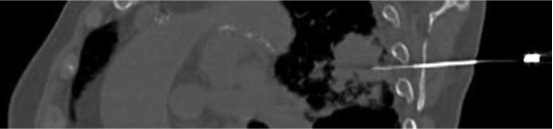

当上后外侧肺结节(UPLN)可能难以通过标准肋间达到时,是否可经肩胛骨CT引导下经皮肺针活检?